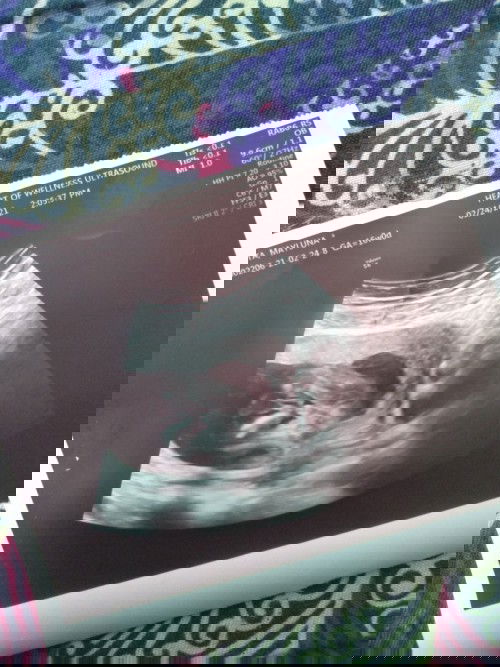

Girl or boy? Gender reveal. 16weeks po. Di maconfirm kasi nakacross leg sya. Answered pls. 🙏😊😁❤️❤

masyado pa po Maaga mhie para Makita gender ni baby kaya wait niyo nlng po mag 22 weeks po Siya

Di nga maconfirm ng sono, kami pa? 😂😂

parang boy